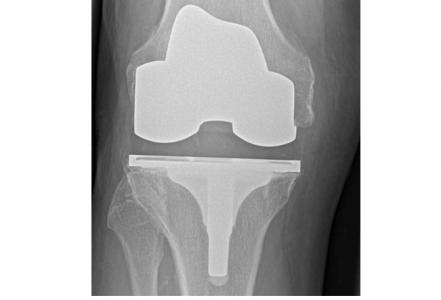

ARTHROPLASTIE de la HANCHE et du GENOU : Un taux de réussite élevé, un résultat durable

80% des arthroplasties du genou et 60% des arthroplasties de la hanche sont toujours en place après 25 ans.

Cette intervention désormais classique permettant de rétablir la forme et la mobilité d'une articulation abîmée ou bloquée, que ce soit l’articulation de la hanche ou du genou, atteint aujourd’hui un taux de réussite élevé, conclut cet examen et cette méta-analyse de la littérature. L’équipe de l’Université de Bristol, après avoir examiné des milliers d'études de cas remontant à 25 ans dans 6 pays, estime pour la première fois la durée probable de ces arthroplasties : 80% des arthroplasties du genou et 60% des arthroplasties de la hanche sont toujours en place après 25 ans. Des données très rassurantes, présentées dans le Lancet.

Des variations considérables en fonction des types d’arthroplasties : un remplacement de la hanche comprend principalement 2 composants (col, cavité) mais reste variable dans la manière dont ces pièces sont fixées à l'os, ainsi que dans les matériaux utilisés pour consolider la surface d'appui. Idem pour l’arthroplastie du genou, l’arthroplastie totale va remplacer toute la surface articulaire du patient, tandis qu'une prothèse de genou unicondylienne ne remplace que la partie endommagée du genou. Bref, les variations sont considérables en matière d’arthroplasties de la hanche et du genou, cependant ces facteurs ont bien été pris en compte dans l’analyse.

Arthroplasties du genou : L’analyse a porté au total sur les données de 299.221 patients, suivis pendant au moins 15 ans, 7.714 patients ayant subi une arthroplastie du genou unicondylienne ou partielle suivis pendant au moins 15 ans également, 88.532 et 3.935 (respectivement) sur 20 ans et 76 651 et 3 935 (respectivement) pendant au moins 25 ans.

• 93% des arthroplasties totales du genou et 77% des arthroplasties du genou unicondyliennes ont duré 15 ans et plus, 90% des arthroplasties totales du genou et 72% des arthroplasties du genou unicondyliennes, 20 ans et plus, 82% et 70% (respectivement) 25 ans et plus.